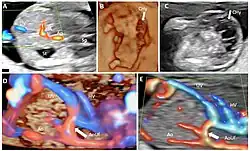

Obstetrícia e genecologia

A ecografia ginecológica examina os órgãos pélvicos femininos (especificamente o útero, os ovários e as trompas de Falópio), bem como a bexiga urinária, os anexos uterinos e a bolsa de Douglas. Utiliza transdutores concebidos para abordagens pela parede abdominal inferior, curvilíneas e sectoriais, bem como transdutores especiais, como a ecografia transvaginal.[6][7][8]

A ecografia obstétrica foi originalmente desenvolvida no final dos anos 50 e 60 por Sir Ian Donald[9][10] e é comummente utilizada durante a gravidez para verificar o desenvolvimento e a apresentação do feto. Pode ser utilizada para identificar muitas condições que podem ser potencialmente prejudiciais para a mãe e/ou para o bebé, possivelmente sem diagnóstico ou com diagnóstico tardio na ausência de ecografia. Atualmente, acredita-se que o diagnóstico tardio acarreta maior risco, se existir, associado à realização de uma ecografia. É desaconselhada a sua utilização para fins não médicos, como vídeos e fotos para "recordações" fetais.[11]

A ecografia obstétrica é utilizada principalmente para: [carece de fontes]

- Datar a gravidez (idade gestacional)

- Confirmar a viabilidade fetal

- Determinar a localização do feto, intrauterina vs ectópica

- Verificar a localização da placenta em relação ao colo do útero

- Verificar o número de fetos (gravidez múltipla)

- Verificar anormalidades físicas importantes.

- Avaliar o crescimento fetal (em busca de evidências de restrição de crescimento intrauterino (RCIU))

- Verificar os movimentos e batimentos cardíacos fetais.

- Determinar o sexo do bebé.